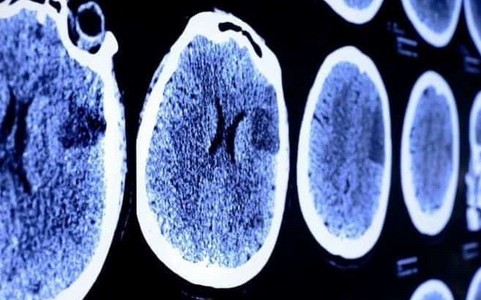

Udar mózgu albo zabiera życie, albo zabiera sprawność. W Polsce atakuje średnio co osiem minut. Nie zna metryki i nie ma litości. Nagle nie działa, ręka, noga, mowa, albo pamięć. I trzeba działać, żeby odzyskać sprawność.